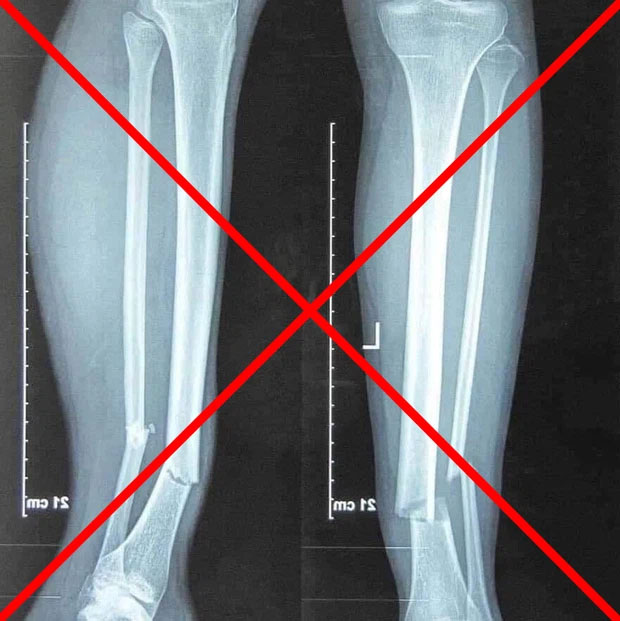

Trong 12 tiếng vừa qua, những thông tin về chấn thương của Hùng Dũng là điều được người hâm mộ bóng đá Việt Nam quan tâm nhất. Cũng vì thế, nhiều hình ảnh, thông tin chưa xác thực được chia sẻ rất nhiều trên mạng xã hội. Trong đó có bức ảnh chụp X-quang phần chân bị gãy được cho là của Hùng Dũng. Tuy nhiên, phía CLB Hà Nội đã phủ nhận thông tin này.

Thực tế đây là bức ảnh chụp của người khác gặp chấn thương gần giống Hùng Dũng đó là gãy xương chày và xương mác ở vùng 1/3 dưới cẳng chân, do đó dễ gây nhầm lẫn.

Bức ảnh chụp X-quang này không phải của Hùng Dũng